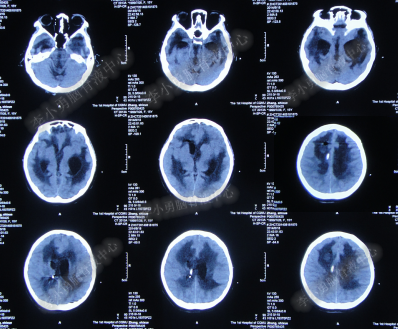

2014年8月31日住入李小勇脑脊液中心,入院时:卧床,表情淡漠,神志嗜睡;体温高37.9°C;头颅枕后正中手术瘢痕,结痂尚未脱落;左枕侧脑室外引流固定在位,尚通畅,可见淡红色浑浊脑脊液引出;颈抵抗,双肺呼吸音粗(图-27);头部CT检查示(小脑肿瘤术后颅内感染病例)脑室系统粘连严重伴双侧颞角脑室扩张明显,双侧侧脑室见引流管影,脑内见多发斑片低密度,中线结构无移位,颅骨术后改变(图-28)。

图-27:2014年8月31日入院时

图-28:2014年8月31日头部CT

入院第4天即2014年9月3日,左枕脑室外引流管引流脑脊液量不多,晨起4:00左右出现血压升高伴瞳孔扩大,4.5:2.0;多参数生理:心率102次/分,呼吸11次/分,血压141/96mmHg,血氧饱和度98%;急行头部CT检查示双侧侧脑室扩大,颞角扩张显著,双侧侧脑室见引流管影,位置变化不大,脑内见多发斑片低密度(图-29)。

图-29:2014年9月3日4点50分头部CT